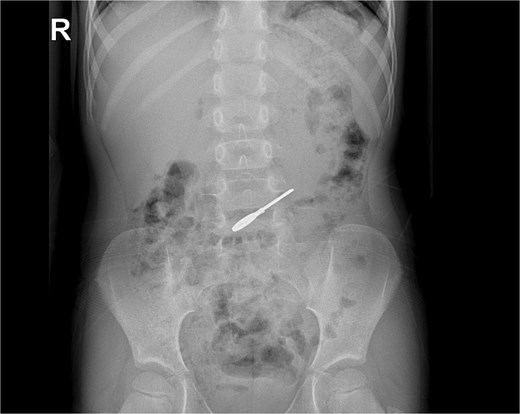

On clinical evaluation, a completely asymptomatic patient was encountered; she was extremely nervous. However, her vital signs were normal, and she had no abdominal pain or tenderness. She passed gas and had no issues with her bowel movements. Due to this, an abdominal X-ray was requested, unveiling a foreign body (small key) in her abdomen. The foreign body appeared to be in her stomach or transverse colon; nonetheless, it did not cause any signs of obstruction (Fig. 1a and b). With these findings, the patient was admitted for close monitoring due to the risk of obstruction. An endoscopy was requested. However, it was completely normal, and the key was nowhere to be found as it had already passed through the pylorus. Another abdominal X-ray was done 48 hours after admission, showing that the foreign body was moving along the intestines (Fig. 2).

After seventy-two hours in the hospital and after close surveillance, the foreign body (key) was expelled with feces without any complications. The kid was discharged, and dietary and care-taking recommendations were given to the parents.